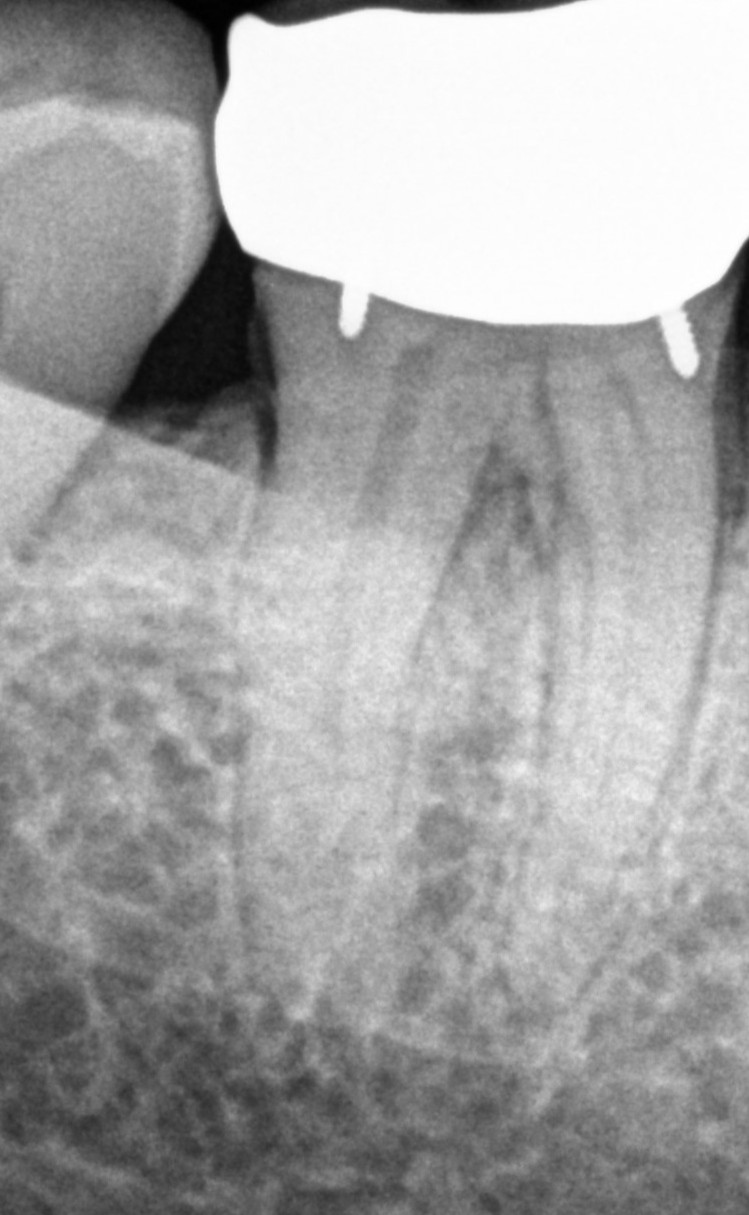

See My Work

Cases